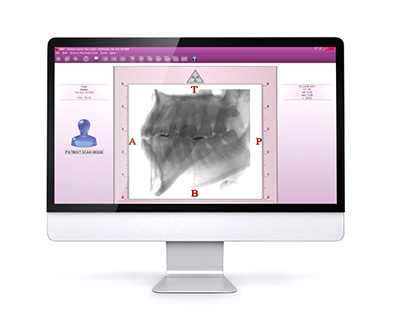

Des performances optimales, un balayage ultra-rapide et un choix complet de projections céphalométriques. Choisissez l’examen le plus adapté à vos besoins diagnostiques.

La plateforme modulaire de Hyperion X9 pro vous permet d’ajouter le module téléradiographique, à tout moment et de manière extrêmement simple. Son bras céphalométrique est un vrai chef d’oeuvre d’ingénierie. Non seulement il est le plus compact sur le marché, mais il est aussi réversible : il peut être monté tant à droite qu’à gauche et, si vos exigences en matière d’espace changent, Hyperion X9 pro CEPH change avec elles. Le capteur PAN/CEPH amovible de dernière génération, associé à un générateur plus puissant, garantit des performances optimales pour toutes les applications. Il sélectionne l’examen le plus adapté aux besoins réels du diagnostic en choisissant entre un balayage ultrarapide ou haute qualité.

Examens téléradiographiques

Projections latéro-latérales avec longueur du balayage sélectionnable

Projection latéro-latérale enfant, avec hauteur réduite, balayage court et dose limitée

Projections FULL CEPH, avec exposition de la thyroïde réduite et calotte crânienne incluse chez les enfants

Projections antéro-postérieures et postéro-antérieures

Projections menton-vertex, y compris les incidences de Waters et de Towne renversées

Projection du carpe

Téléradiographie

Latéro-latérale : avec détails des os et des tissus mous en évidence, fondamental pour les études céphalométriques.

Téléradiographie

Antéro-postérieure : pour investiguer les asymétries et les malocclusions en vue d’un traitement correct.